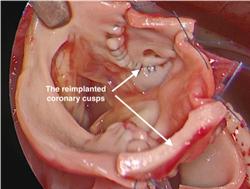

Los velos coronarios se implantan en la aorta del neonato. Las imágenes son cortesía del Dr. Redmond Burke.